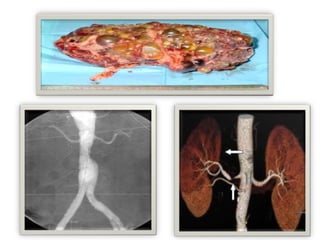

• Renal mass in polycystic kidney disease(PKD)

• Audible bruits in: renal artery stenosis or abdominal aortic aneurysm

Renal

• PKD

• Renal artery stenosis

 Unilateral small kidney by any radiographic study

 RenalA. stenosis:

• Renal angioplasty for fibromuscular dysplasia

• Renal stenting for bilateral artery stenosis